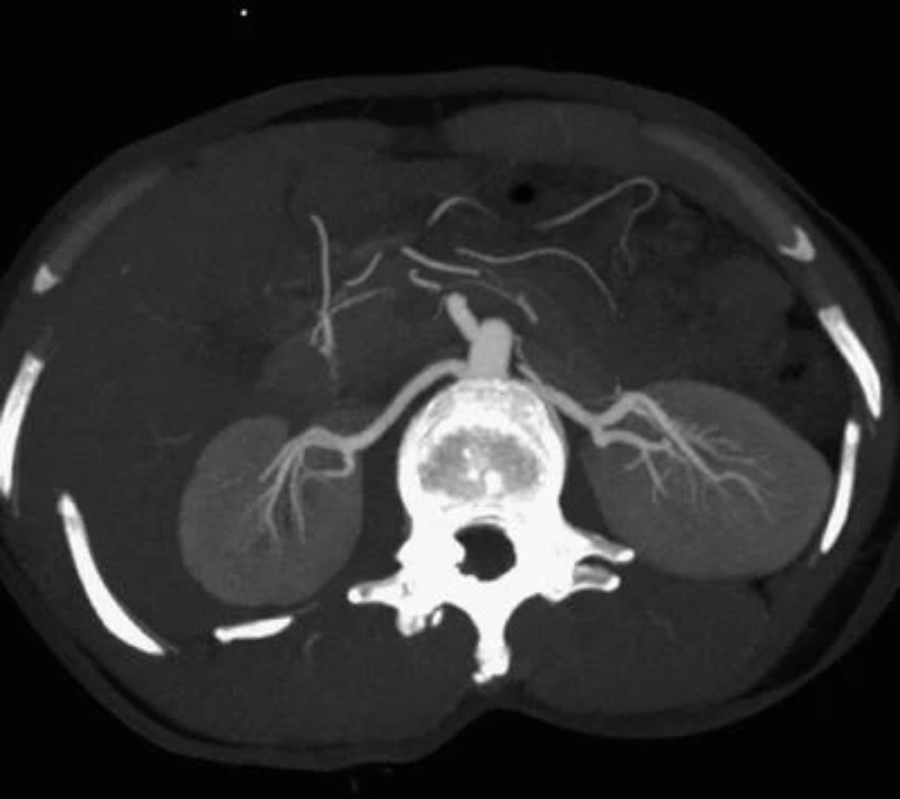

每个主要的肾动脉通常会产生前部和后部(图41.3)。前部进一步细分为四个节段分支,供应上极和下极以及肾脏的前上部和中部。后部供应肾脏剩余的后部区域。在超过50%的肾脏中,后段动脉位于肾后表面的中部或上半部,可能因上肾盏过度内侧穿刺而损伤。6节段动脉进一步细分为大叶动脉、叶间动脉、弓形动脉,最后是小叶间动脉。Brödels 线是在后外侧前部和后部血液供应之间运行的无血管平面。因此,后花萼的外周末端穿刺可以最大限度地降低 PCNL 期间出血的风险,这仅仅是因为它最大限度地降低了血管损伤的风险。

肾脏解剖:肾脏血管的 CT 血管造影;双侧肾动脉前、后分支清晰可见